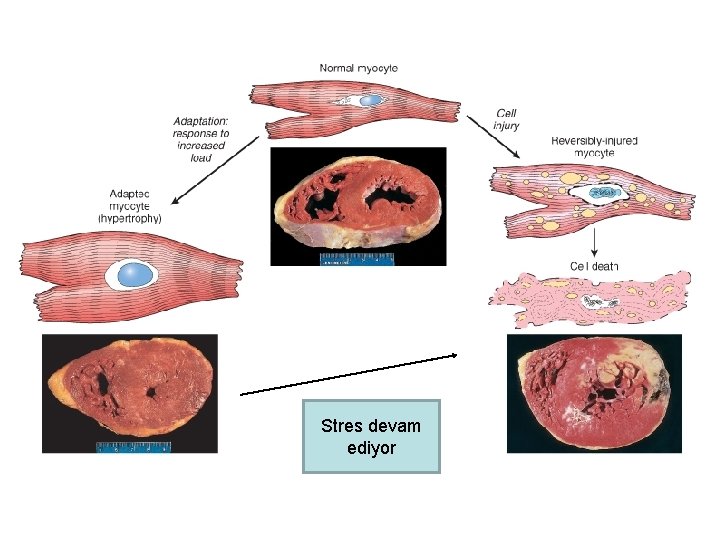

HİPERTROFİ • Hücre boyutlarında artış Organ boyutlarında artış • Bölünme yeteneği olmayan hücrelerde görülen uyum yanıtı Ör: Kalp kası, İskelet kası 1. Fizyolojik (sporcularda çizgili kas hipertrofisi) 2. Patolojik (Hipertansiyon veya aort kapak hastalığı nedeniyle kalp hipertrofisi)

Stres devam ediyor